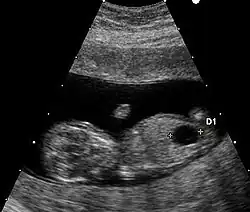

| Przezierność karkowa/badanie wolnej jednostki beta hCG/PAPPA | 11–13,6 | 91%[a] | 5%[a] | W badaniu wykorzystuje się technikę ultrasonografii do zmierzenia przezierności karkowej w połączeniu z badaniem wolnej beta hCG i PAPPA (ang. pregnancy-associated plasma protein A). Amerykańskie National Institutes of Health potwierdziło, że to badanie w pierwszym trymestrze ciąży jest bardziej dokładne niż metody przesiewowe w drugim trymestrze[25]. |